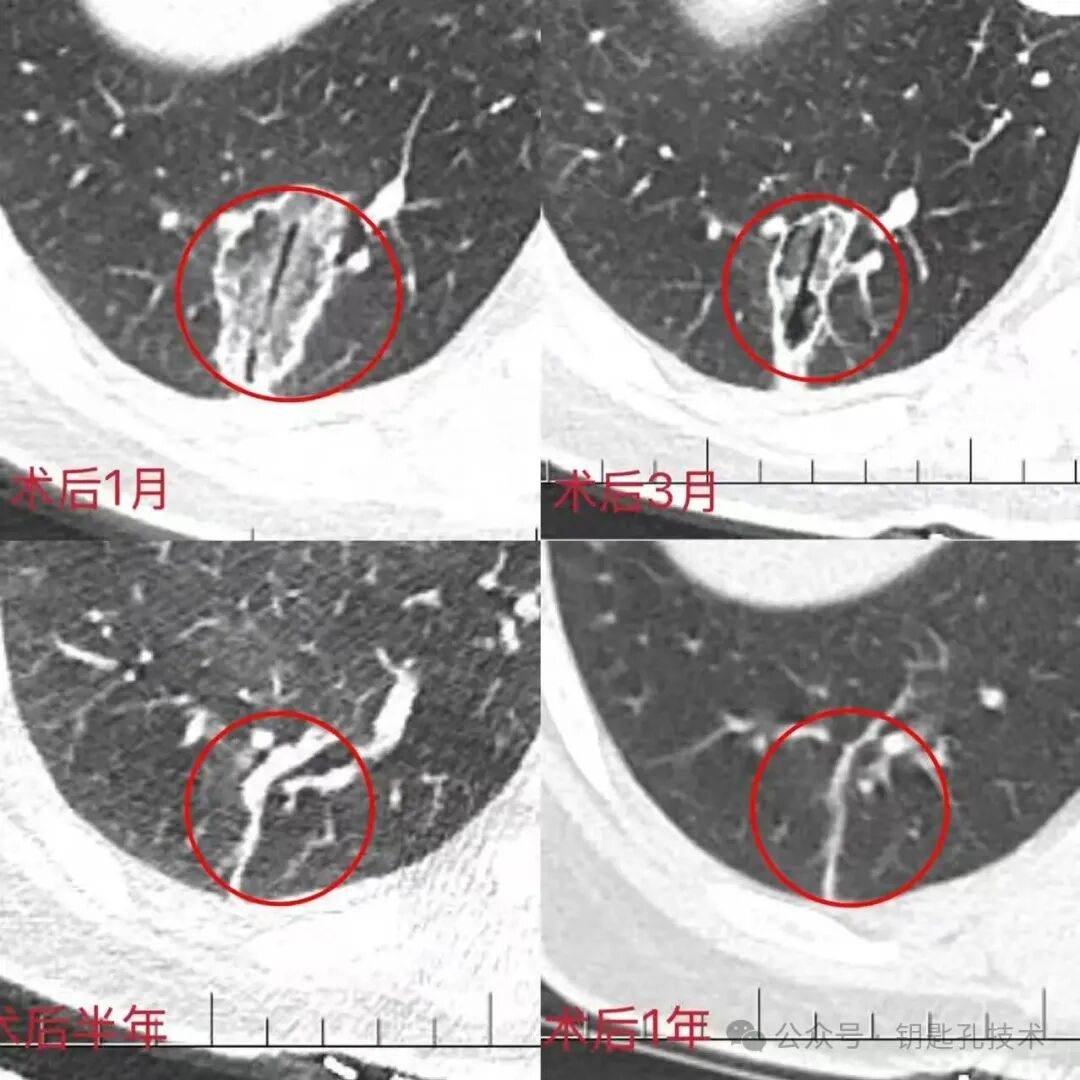

图3: 术后一月复查 反应带消失,边界清晰 (病理示:腺癌)

术后三、六月复查 范围持续变小,增强扫描未见明显强化

术后一年 完全吸收、纤维化,呈现为条状瘢痕